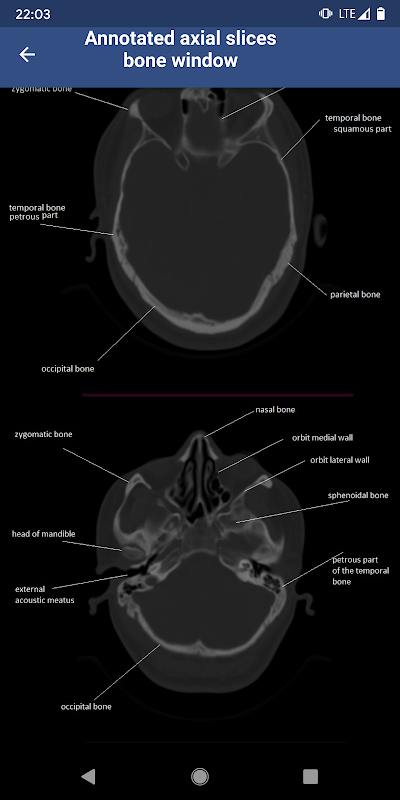

This application aims to help medical students read brain CT scans and recognize the normal appearance of the brain in CT. it is for educational purposes only

• Brain CT : annotated slices syot layar 1

• Brain CT : annotated slices syot layar 2

• Brain CT : annotated slices syot layar 3